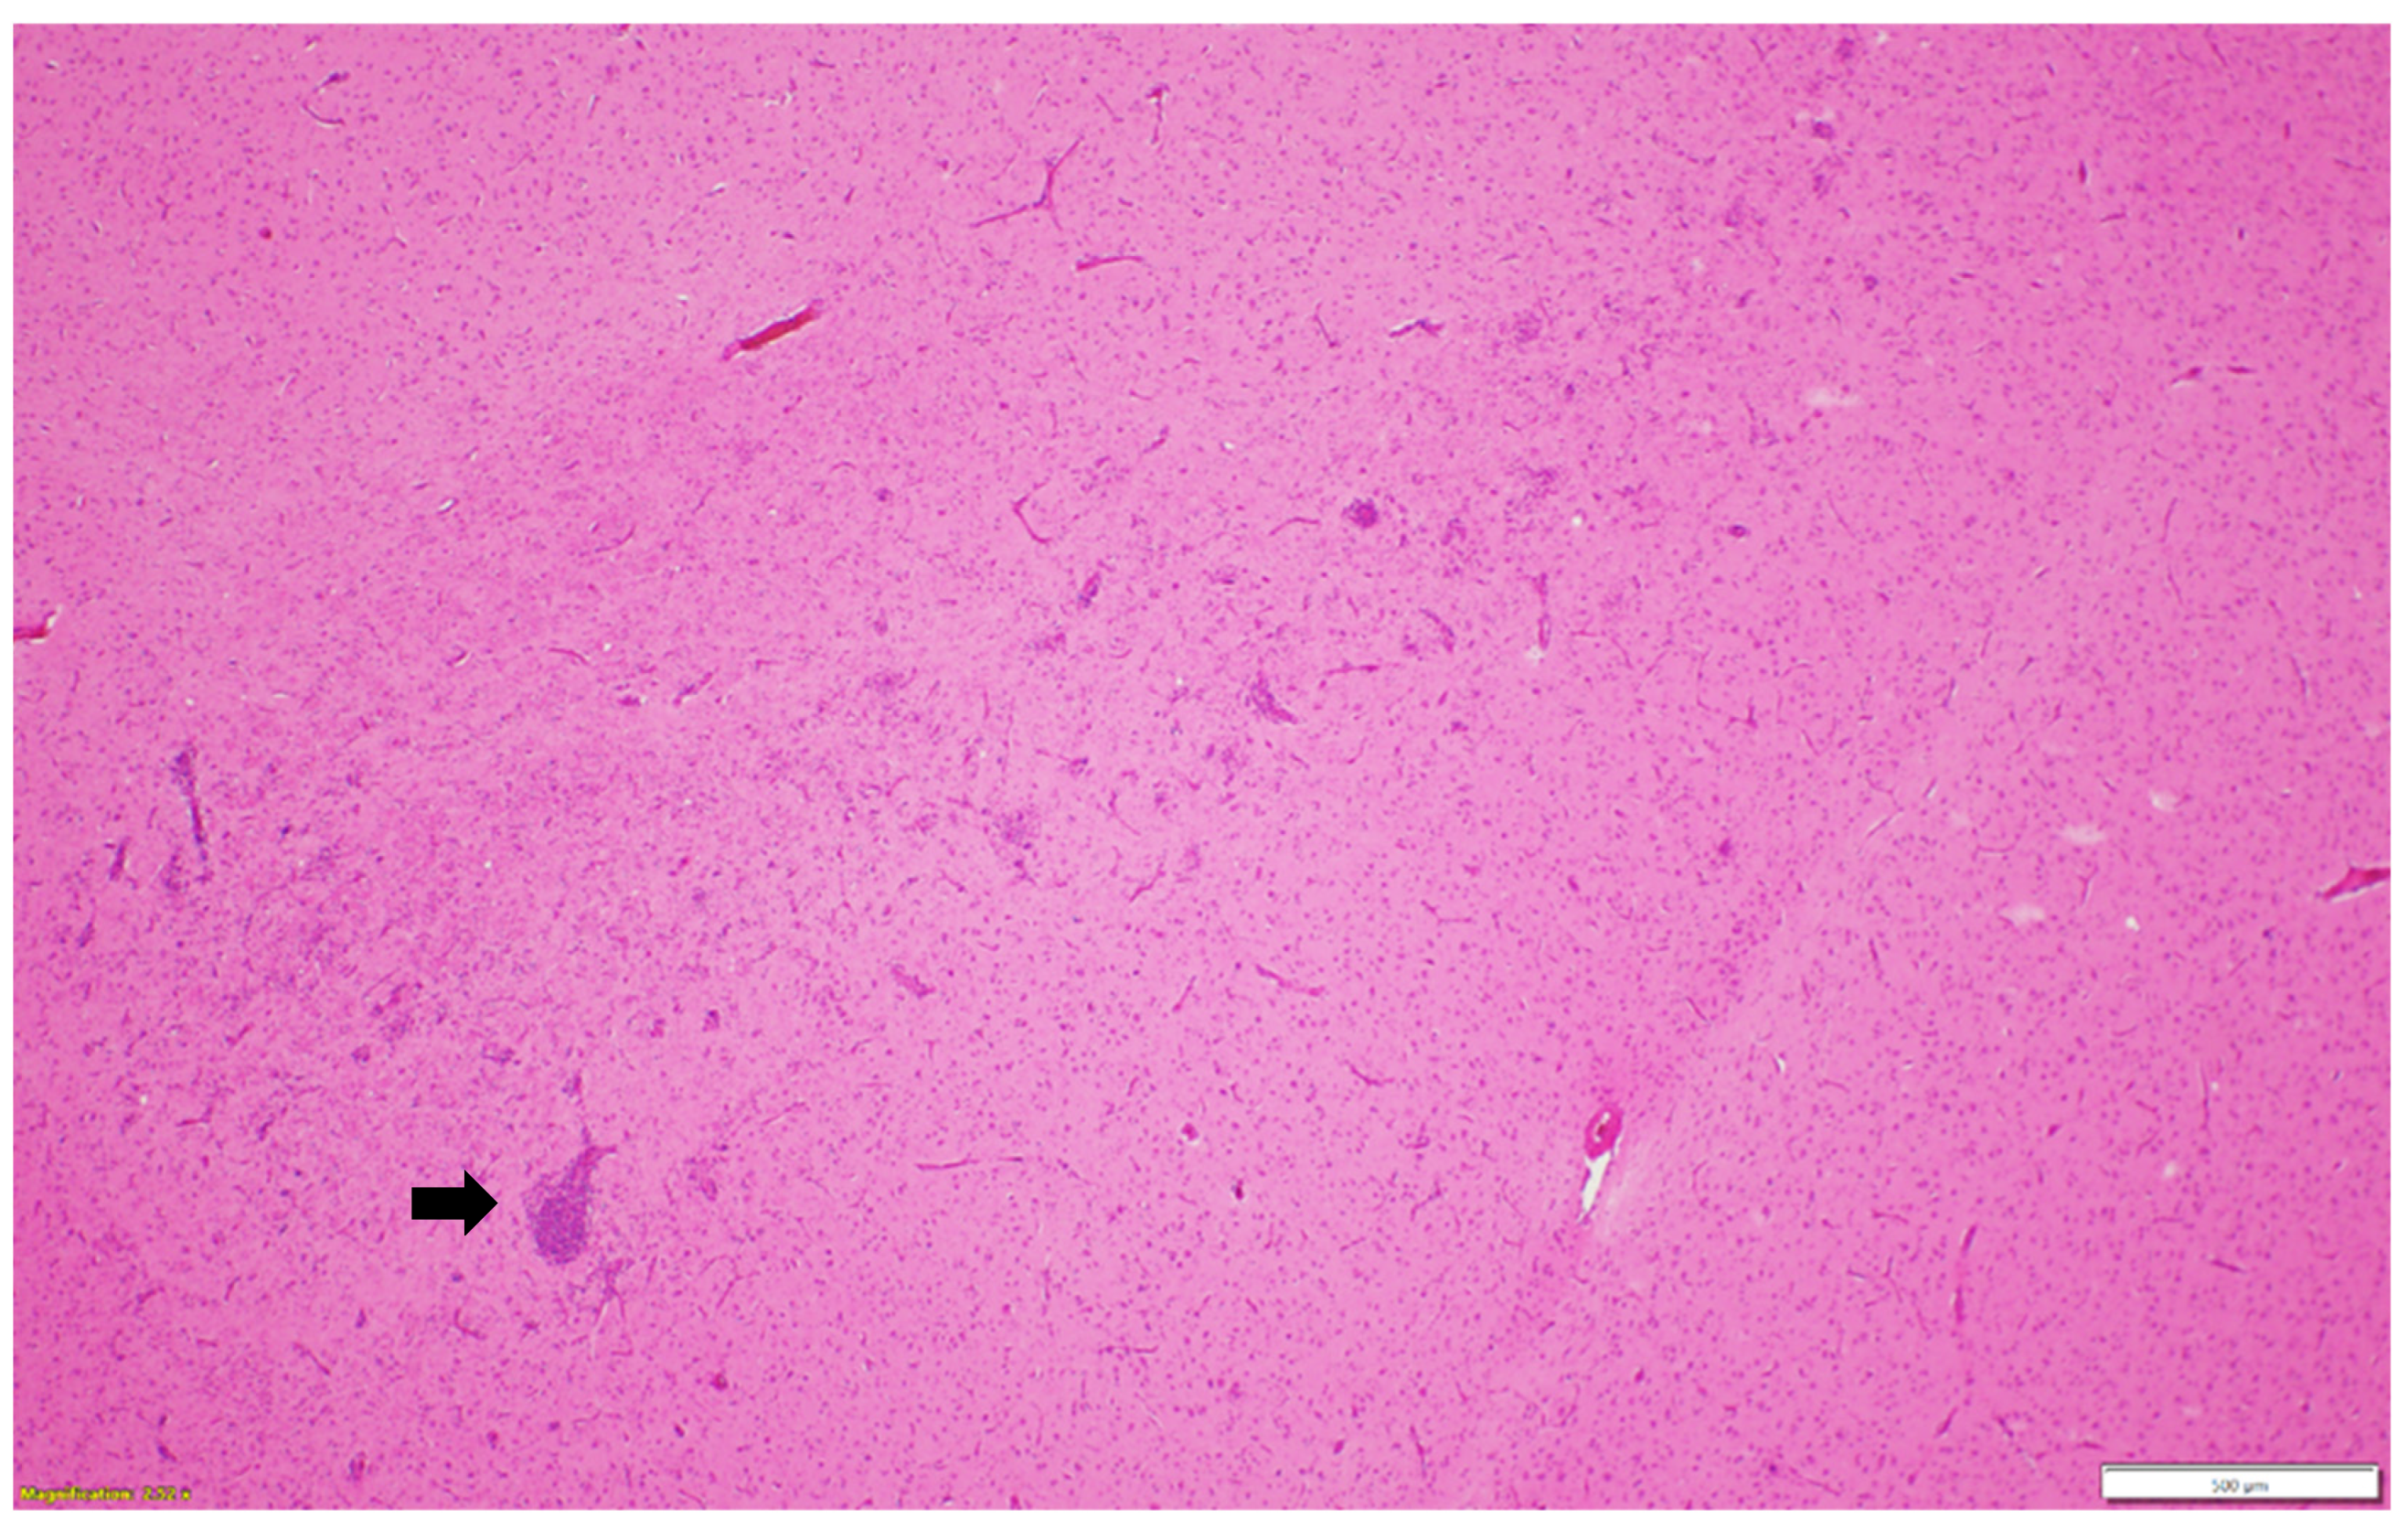

Microscopic examination of different brain, spinal cord, peripheral nerves, and ganglions sections revealed multifocal areas of lymphoplasmacytic and histiocytic infiltrates, indicating encephalitis (Figure 1) in the cerebral white matter, thalamus, hippocampus, and medulla oblongata close the ventricular space. The inflammatory cells around the vessels (perivascular cuffing) as well as around the neurons (satellitosis and neuronophagia) resulted in several neuronal degeneration and central chromatolysis (Figure 2). The gray matter in the spinal cord had multifocal lymphoplasmacytic infiltrates, indicating myelitis (Figure 3). In addition, there was mild to moderate multifocal ganglioneuritis in the pelvis ganglions (Figure 4).

Figure 1. Multifocal lymphoplasmacytic encephalitis and perivascular cuffing (black arrow) in the cerebral white matter. Paraffin-embedded tissue was stained with hematoxylin and eosin.